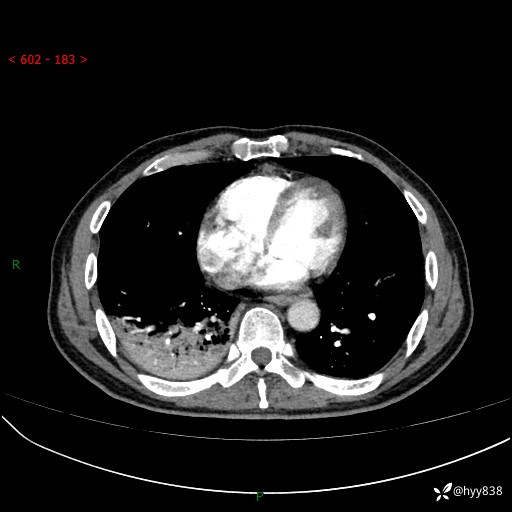

63岁/男,发热5余天。精彩好病例,“大叶性肺炎”,等你来诊---结果公布~

【患者信息】:63岁/男

【主诉】:发热5余天

【现病史及既往史】:患者5余天无明显诱因出现畏寒寒战发热,最高体温39.5℃,发热无明显昼夜规律,伴全身乏力、头晕,无头痛、无咳嗽咳痰、无胸痛咯血、无气短、无腹痛腹泻、无尿频尿急尿痛等不适,于当地市第五人民医院就诊,予以抗感染等治疗(具体不详)后发热无明显好转,1天前查胸部CT提示右下肺感染,为求进一步诊治,门诊以“社区获得性肺炎”收治入院; 起病以来,患者精神、食欲一般,睡眠可,大小便正常,体力体重较前无明显变化。

【检查】:胸部CT增强